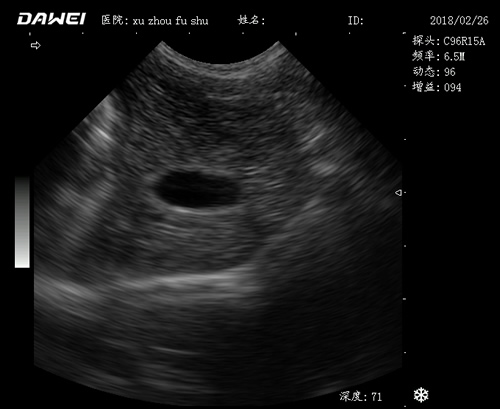

應(yīng)用范圍:

·中小動(dòng)物的肝、膽,脾、腎、膀胱、子宮、妊娠等各組織器官的檢查和病變的診斷